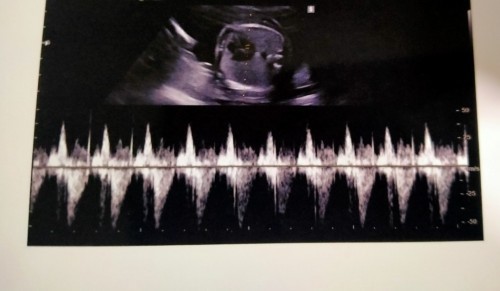

21W 4D หมูน้อยของหม่าม๊า

คุณหมอบอกว่าหัวใจหนูเต้นดีมากๆ และหนูก็ดิ้นเก่งด้วยจ้า 👧🐷♥️ #ทีมลูกสาวจ้า #ทีมพฤษภาคม64